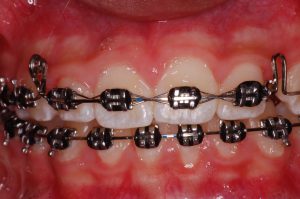

As discrepâncias esqueléticas verdadeiras, sobretudo as anteroposteriores, apresentam, na sua maioria, compensações dentárias em diversos graus. Normalmente nas Classes III de Angle observa-se uma protrusão dos incisivos superiores e a retroinclinação dos inferiores. Já nas Classes II, essa compensação apresenta-se numa relação inversa, onde os incisivos inferiores posicionam-se protruídos e os superiores retroinclinados.

Essas posições dentárias podem ser consideradas como uma tentativa natural de busca de equilíbrio entre os arcos dentários, o que pode mascarar pequenas discrepâncias esqueléticas, mas tornam-se ineficientes nas moderadas e severas. Nesses casos, um planejamento orto-cirúrgico restabelece não apenas o equilíbrio dentário, mas também o esquelético e, principalmente, o facial.

Compensação natural na Classe III